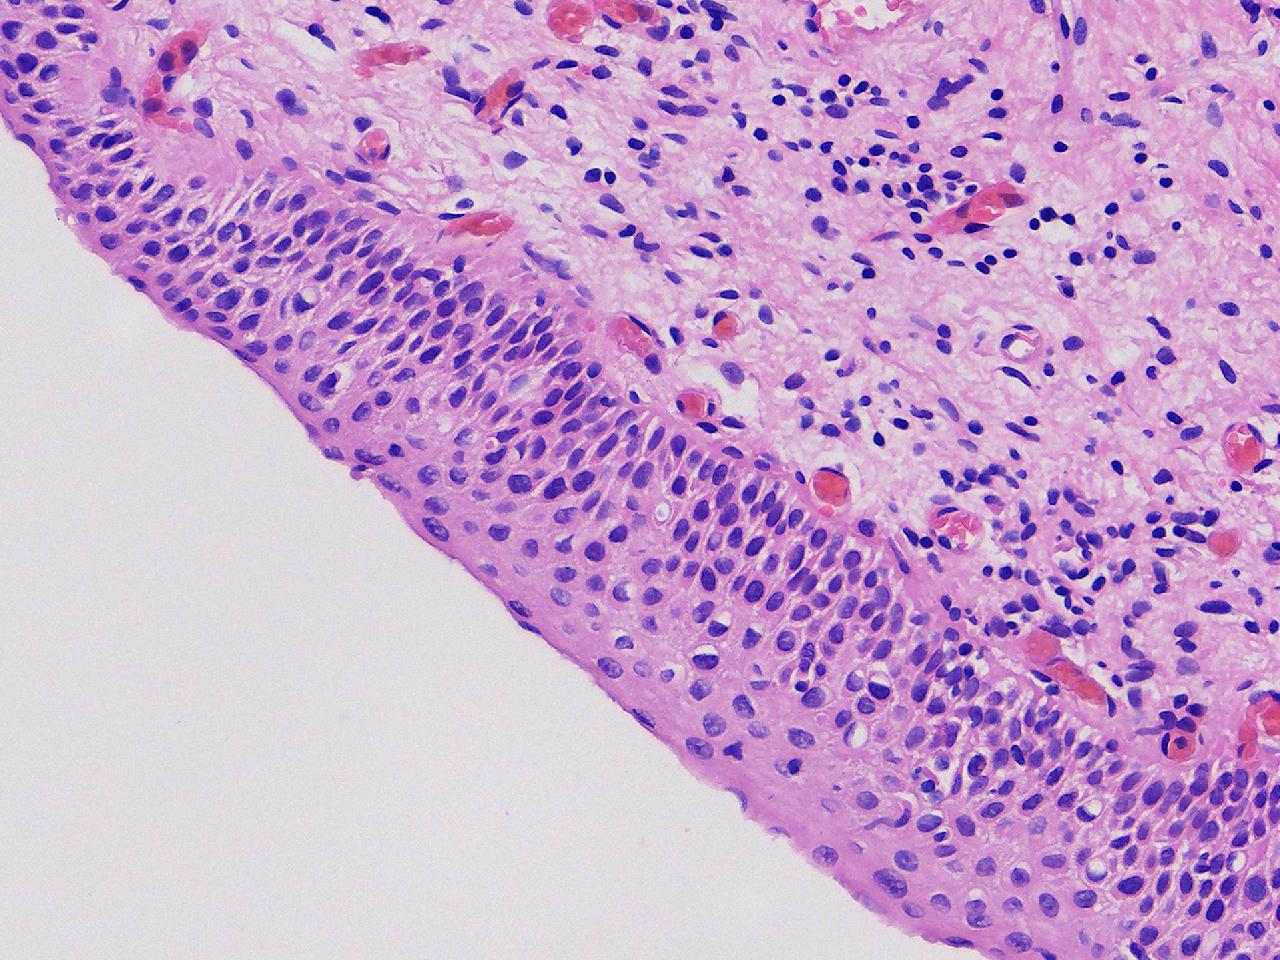

CIN1级? CIN2级?

性别年龄61岁临床诊断

一般病史女,61岁,宫颈活检,,HPV6+ 52+

标本名称宫颈活检

大体所见灰白色不整形软组织1块,直径0.3厘米。

CIN2倒是不够,图3有几个像挖空细胞,HPV有阳,勉强可以考虑小灶LSIL。

• zhuang xia nan:  是的。  2级肯定不够,有挖空细胞,小灶1级。    谢谢老师指点。

CIN1.